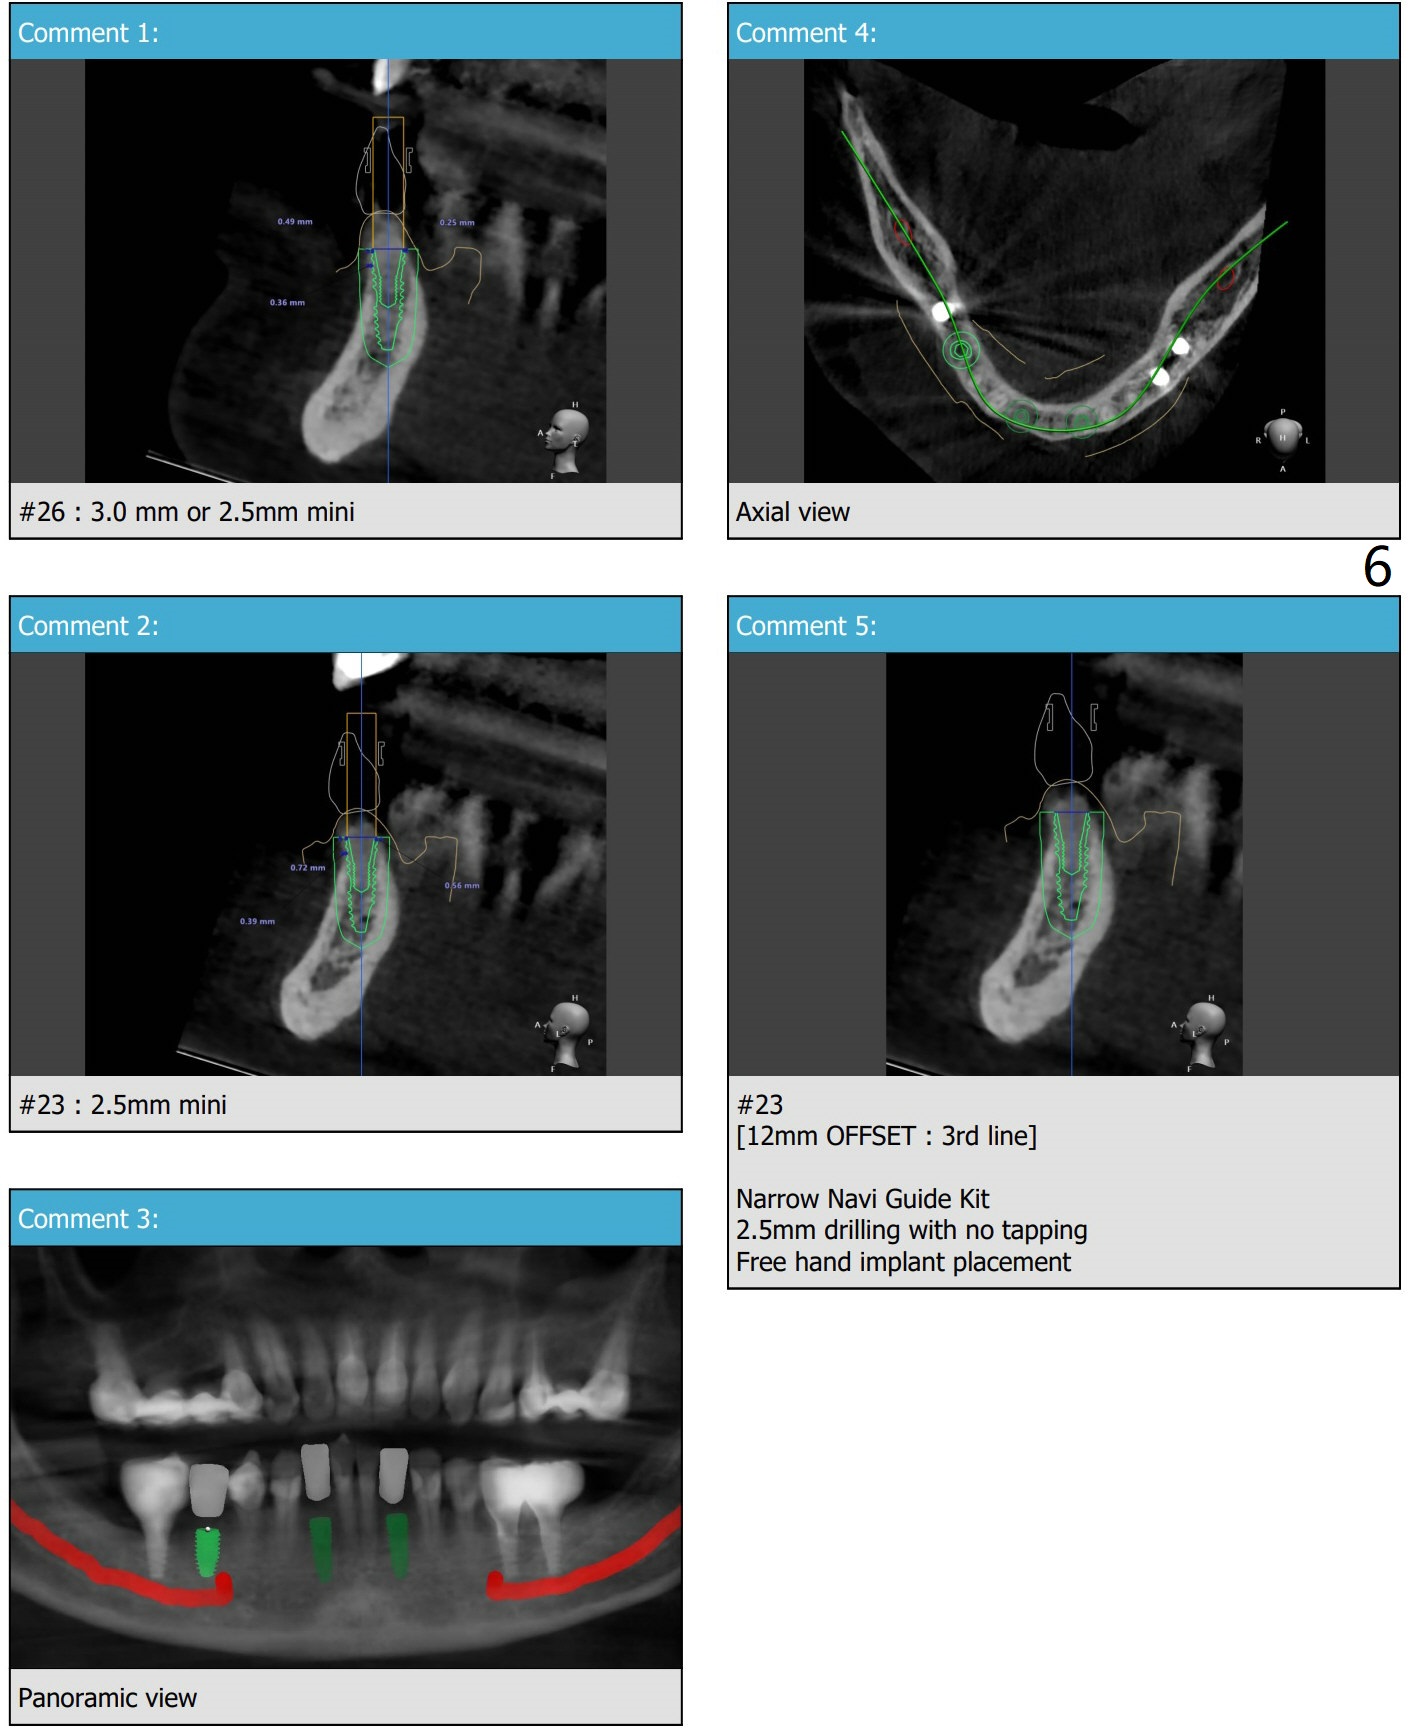

导板钻洞徒手植入

57岁女